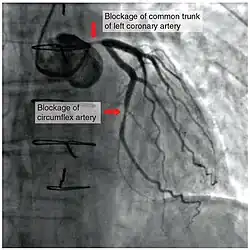

To diagnose a coronary occlusion, a doctor may view a patient's medical history, or perform a coronary angiography; a doctor will stick a catheter into the wrist or groin, lead it to the heart, and inject a liquid for X-ray imaging.[4]

To assist in a diagnosis, healthcare providers may also order a electrocardiogram (ECG or EKG), coronary calcium scan, stress test, cardiac magnetic resonance imaging (MRI), cardiac positron emission tomography (PET), invasive coronary angiography, and/or coronary CT angiography.[11]